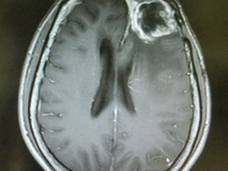

Researchers Use AI-based Modeling to Assess Treatment and Predict Survival from Glioblastoma

See how these NCI-funded researchers working with artificial intelligence (AI) used information from a survival model to refine treatment for glioblastoma.